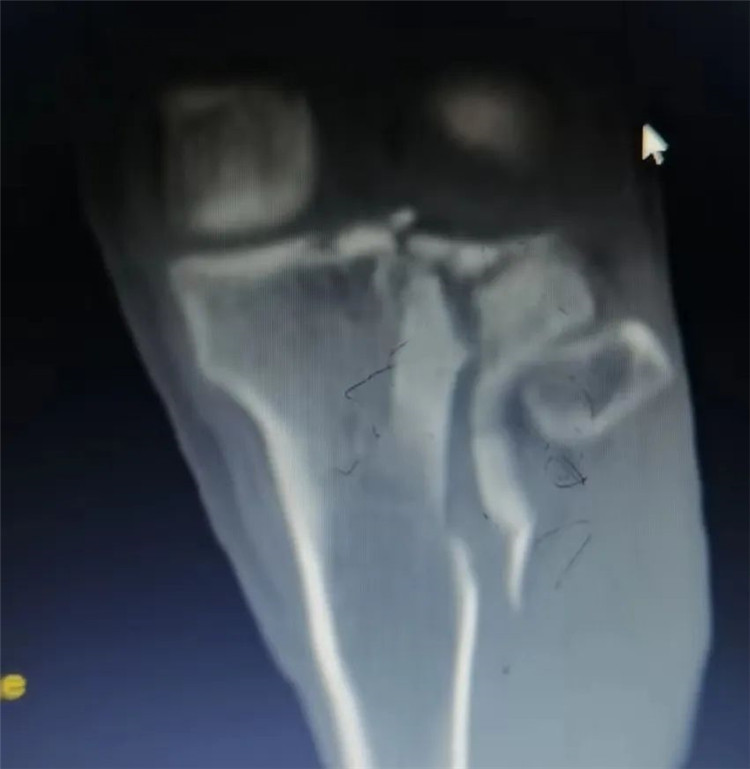

术中镜下见游离骨块复位,损伤半月板成形好